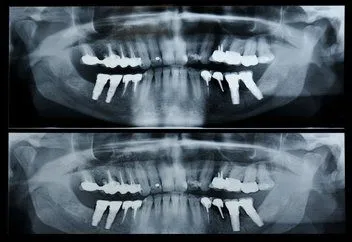

panorex x-ray

A panorex is a very impressive piece of imaging machinery in that it is capable of identifying many issues and structures that a normal x-ray is not. Initially you will sit in a chair with your chin on a small ledge. Once positioned in the machine, it will rotate around your entire head taking a full 360 degree view of the teeth, head, sinuses and bones.

The ability to view the full structure of your head as a whole is very informative to the dentist. It will allow us to see any potential problems and make sure that everything is functioning as it should be. The panorex is capable of viewing specific types of structural problems, infections or asymmetry among many others.